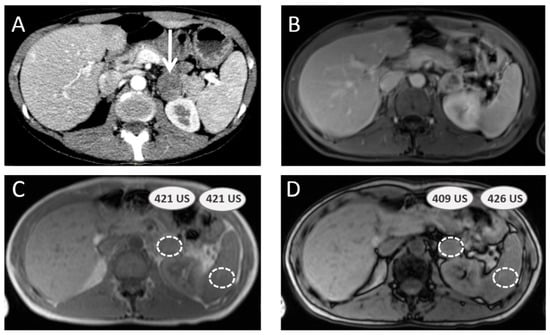

3.3. Additional Value of Magnetic Resonance Imaging with Chemical Shift Imaging

3.4. Pheochromocytomas and Paragangliomas: Variable Morphological Characteristics Using Anatomical Imaging